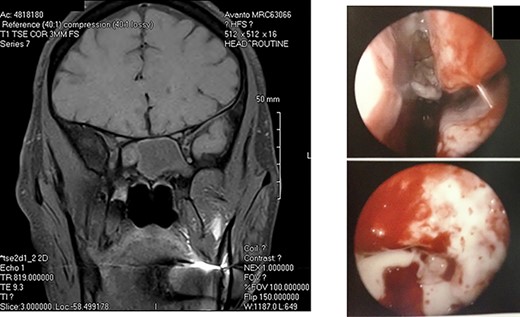

A: Magnetic resonance imaging (coronal view) reveals an expansile sphenoid sinus mass with fluid characteristics with extension into the cavernous sinus on the right. B: Intra-operative view through an endoscope reveals mucopurulent material from right sphenoid ostium. Sphenoid sinus reveals clumps of extramucosal ‘peanut buttery’ visco-elastic material (allergic mucin).

A diagnosis of right posterior cavernous sinus syndrome was made, and patient was subjected to imaging. CT scan revealed complete opacification of sphenoid sinus with bony erosion. MRI of brain revealed an expansile sphenoid sinus mass (with fluid characteristics on restricted diffusion) indicative of a pyo-mucocele (Fig. 2A). Complete blood counts were within normal limits and erythrocyte sedimentation rate was 95 mm/hour. Immunological work-up including serum anti-nuclear antibody, anti-cytoplasmic antibody and HIV were negative. Blood cultures were negative for bacteremia and fungemia. Patient was started on intravenous vancomycin, fluconazole and Decadron (Merck & Co., Inc., Whitehouse Station, NJ) was added after 48 hours. Five days after initiating treatment, no response was noted.

Diagnosis of AFS is based on history of type I hypersensitivity, presence of nasal polyposis, characteristic CT and MRI findings, presence of ‘allergic fungal mucin’ intra-operatively and staining for fungal hyphae on histopathology [4]. MRI findings (T1 central hypointensity and T2 central signal void) when combined with CT is highly specific [1]. However, histopathology can be inconclusive as yield is variable [5]. Diagnosis in our patient was based on the characteristic imaging and intra-operative findings.